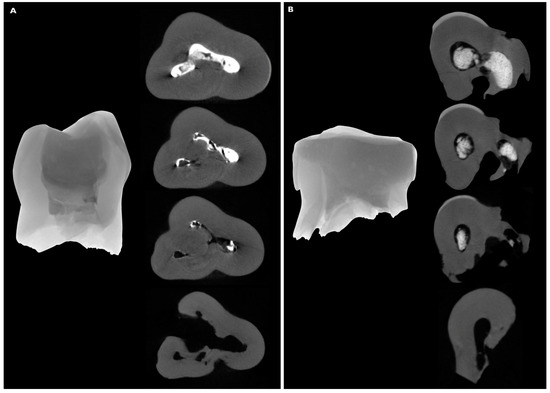

2. Materials and Methods

3. Results